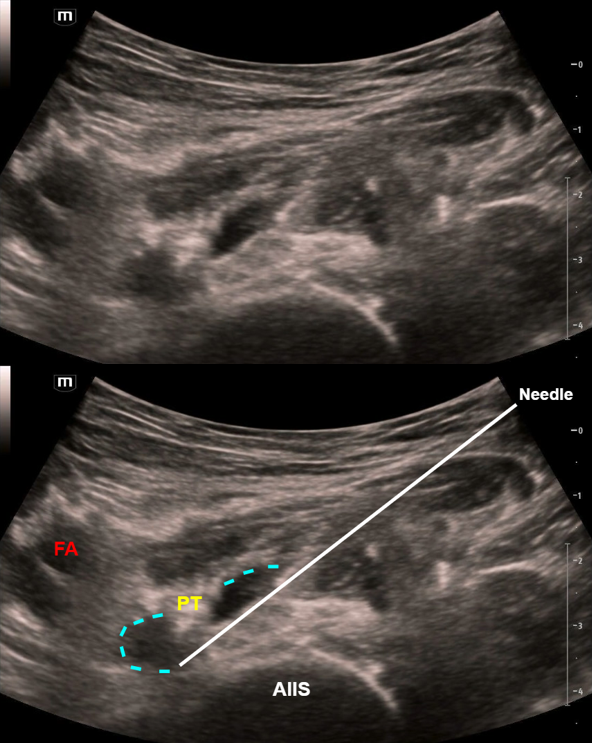

Above we can see the important anatomical landmarks of the pericapsular nerve group (PENG) block. The femoral artery and veins (FA, FV) were identified using color doppler as shown. The bony land marks are the anterior inferior iliac spine (AIIS) and iliopubic eminence (IPE), with the ilium in between. The psoas tendon (PT) is seen along the groove created by the iliopsoas notch.

Here we can see the needle inserted under the psoas tendon with injection of local anesthetic which hydrodissects, or lifts, the psoas tendon off the bone. The spread of the local anesthetic is indicated by the dotted blue line.